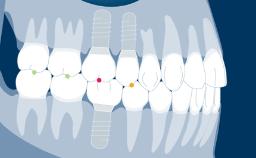

Prosthodontic Planning Principles for Implant Placement

Regardless of the location or extent of treatment, the planning of implant therapy should always be prosthodontically driven.

This ensures that the implant placement will serve the needs of the prostheses and will be compatible with the desired end result.

With the aim of achieving an optimal outcome, the prosthodontic planning should include consideration of all relevant prosthodontic factors and an appropriate diagnostic work-up as the basis for the specific planning of implant prostheses and supporting implants.